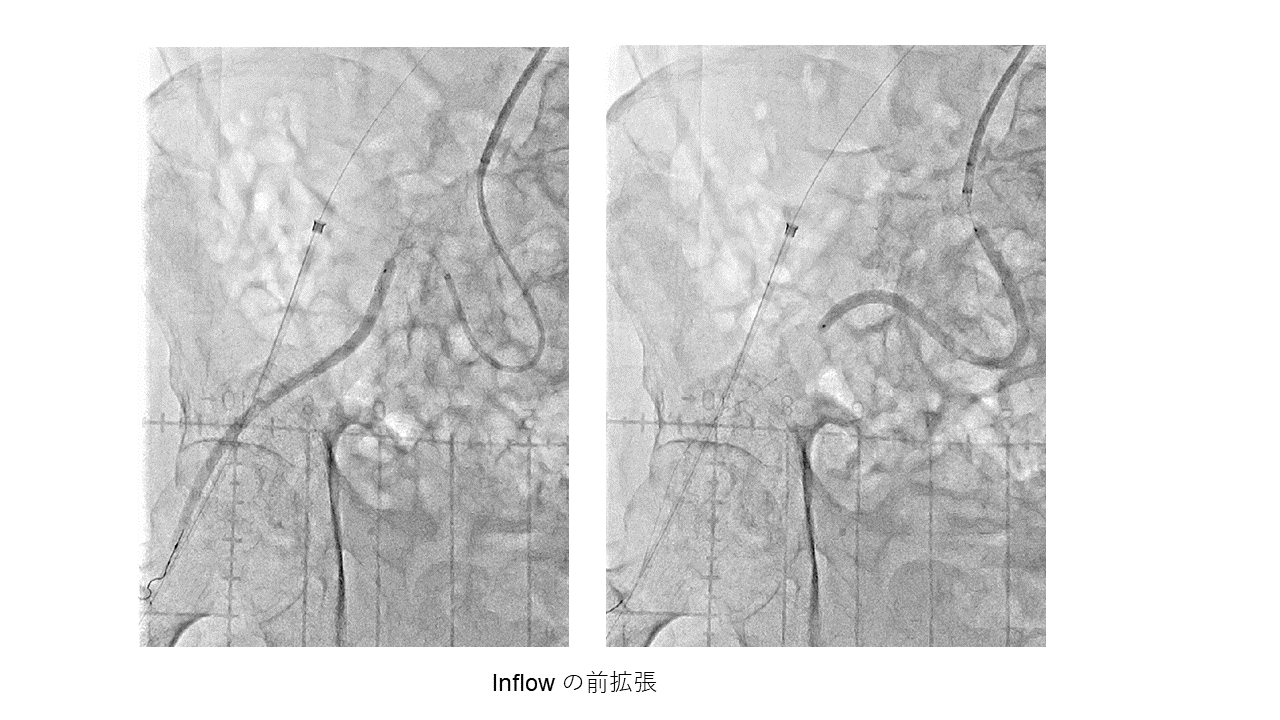

症例は70代男性、糖尿病性腎症で維持透析中である。右足趾の虚血性潰瘍を認めた。SFAにびまん性高度狭窄、ATA、PTAに高度石灰化を伴うCTOを認め、EVTの方針となった。午後6時に手技を開始した。ATAは石灰化に阻まれアンテからのワイヤー通過は不能、足背動脈を穿刺し、プルスルーを確立しバルーン拡張を行った。しかし、アンテのワイヤーが足背動脈遠位に通過せず、穿刺部での血管損傷のためATAから足背動脈への血流が途絶えてしまった。PTAは閉塞しているが、側副血行路経由で足底動脈の血流は確認できたため、SFAの治療を行い手技終了の予定とした。しかし、SFAをDCBで拡張したところ、遠位塞栓により足首以下の血流が消失した。繰り返し血管拡張薬を投与するも血流の改善認めなかった。そのため、PTAへのEVTを追加する方針とした。この時点で午後11時半であった。アンテからのワイヤーは通過せず、石灰化を目印にPTA遠位を穿刺し、ワイヤー通過に成功した。バルーン拡張後はPTAから足底動脈への血流が得られ、午前3時に手技を終了した。